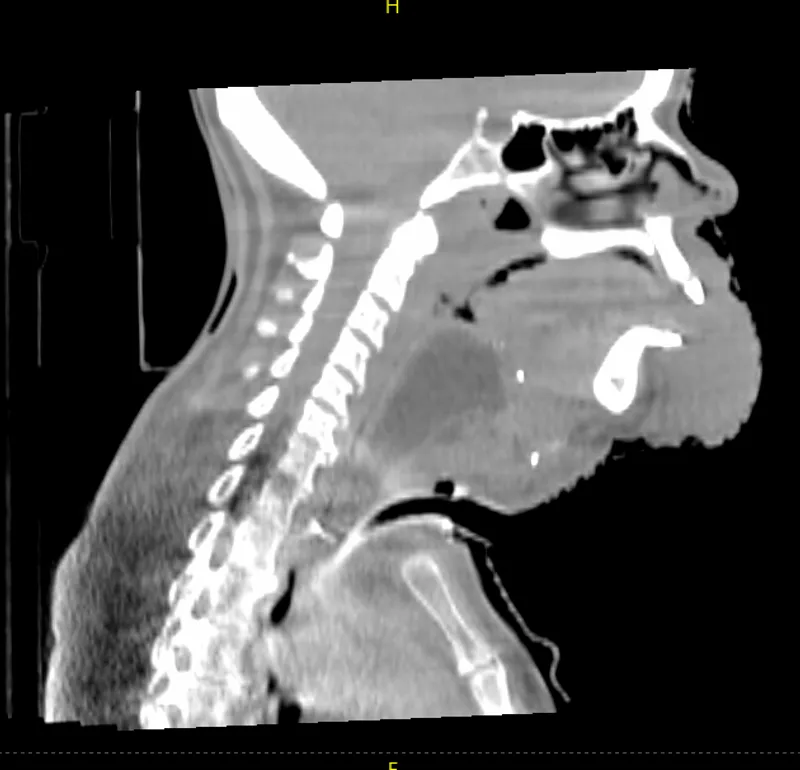

Head and Neck

In this head and neck case with extensive disease involvement, the larger FOV delivered by HyperSight on a Varian TrueBeam system provides greater visibility of the structures and organs surrounding the target to enable a more accurate positional alignment. In this case, the clinician is able to visualize all pertinent anatomy without the need to acquire additional images. This potentially means less time on the treatment couch, less time in the immobilization device, and less imaging dose to the patient.

Hypersight head and neck

Image courtesy of University of Maryland Medical Center, Baltimore, Maryland.